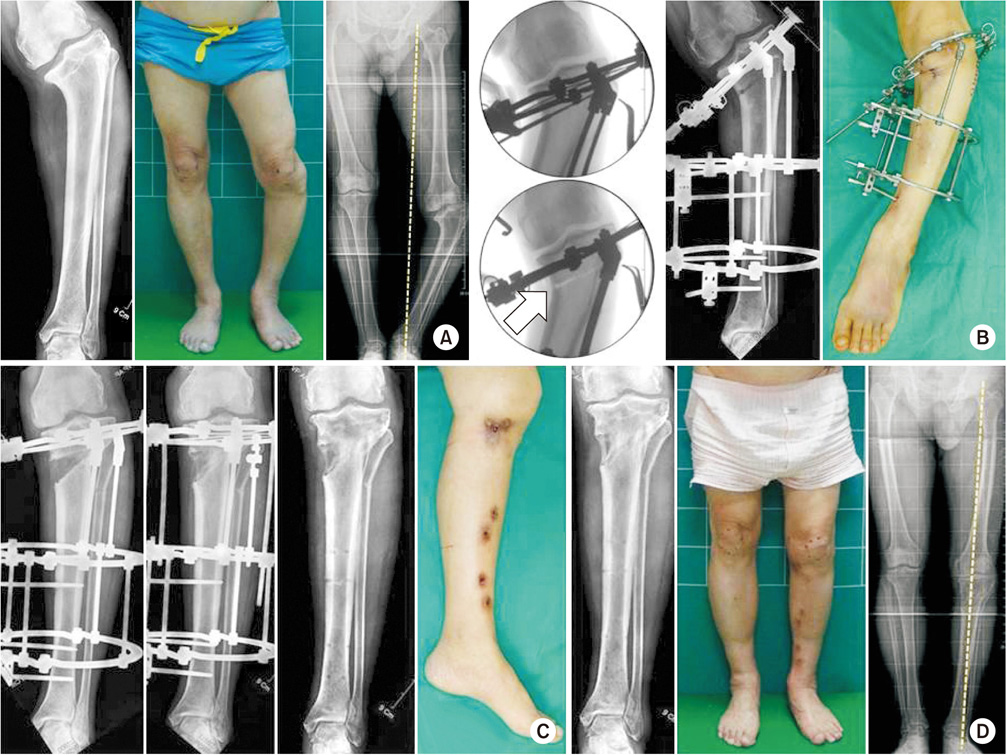

Fig. 6

(A) A 67-year-old man, who was suspected to have growth plate injuries in childhood, was confirmed to have varus deformity in the left proximal tibia, and mechanical axis was shifted medially. (B) Because center of rotation of angulation was very close to the joint, fixing the plate was difficult and the correction angle was high; hence, acute correction was expected to be difficult. After attaching the Ilizarov external fixator, osteotomy was performed with the hinge placed outside the convexity (arrow). (C) A progressive distraction was performed to correct the varus deformity, and the external fixator was removed 5 months after sufficient bone maturation. (D) After about 10 months postoperatively, we confirm that the mechanical axis was more improved than before surgery.

jkfs-30-219-g006.jpg

Fig. 6 (A) A 67-year-old man, who was suspected to have growth plate injuries in childhood, was confirmed to have varus deformity in the left proximal tibia, and mechanical axis was shifted medially. (B) Because center of rotation of angulation was very close to the joint, fixing the plate was difficult and the correction angle was high; hence, acute correction was expected to be difficult. After attaching the Ilizarov external fixator, osteotomy was performed with the hinge placed outside the convexity (arrow). (C) A progressive distraction was performed to correct the varus deformity, and the external fixator was removed 5 months after sufficient bone maturation. (D) After about 10 months postoperatively, we confirm that the mechanical axis was more improved than before surgery.